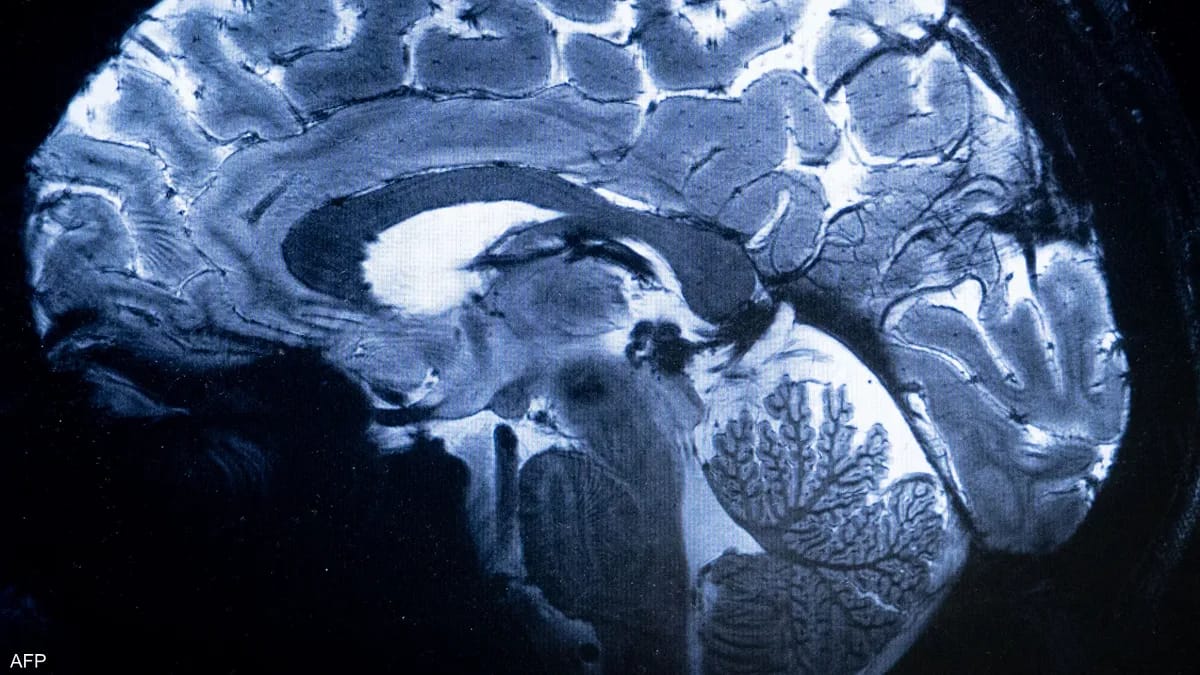

تووشبوون بە کۆرۆنا دەبێتە هۆی هەوکردنی مێشک، وێنە: سکای نیوز

زانیاری بەدەستهاتوو: توێژینەوەیەک کە لە گۆڤاری زانستی "Brain" بڵاوکراوەتەوە، دەریدەخات کاریگەری ڤایرۆسی کۆرۆنا لەسەر کەسی تووشبوو دەمێنێت و دەبێتە هۆی هەوکردنی سەنتەری کۆنتڕۆڵی مێشک، ئەمەش دەبێتە هۆی هەناسەتەنگی و ماندووبوون و دڵەڕاوکێ.

لێدوانی فەرمی: د. کاترینا ڕۆی، پسپۆری مێشک لە زانکۆی کامبریج دەڵێت: کەسی تووشبوو بە ڤایرۆسی کۆرۆنا، بۆ ماوەیەکی درێژخایەن نیشانەکانی لەسەر دەمێنن، ڤایرۆکەسە دوای چەند ساڵێک تاوەکو ئێستا کاریگەری لەسەر دەیان ملیۆن کەس ماوە و کێشەی هەناسەدان و جووڵەی خوێنیان هەیە.

بۆچی گرنگە: ئەم توێژینەوەیە دەریدەخات؛ تووشبووانی ڤایرۆسی کۆرۆنا دوای چاکبوونەوەیان بۆ ماوەیەکی زۆر کاریگەری نەرێنی ڤایرۆسەکەیان لەسەر دەبێت، بەتایبەت لەسەر هەوکردنی مێشک، ئەمەش وا پێویست دەکات ڕێکارەکانی خۆپارێزی چڕتر بکرێن.